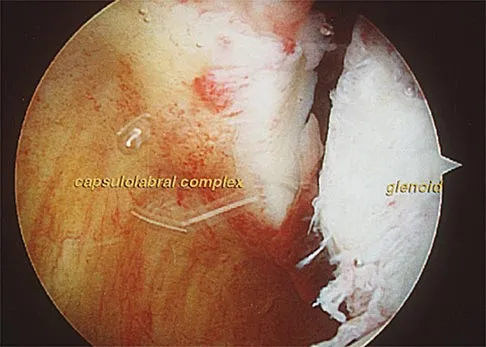

Question 44

A 22-year-old wrestler who underwent an open anterior shoulder reconstruction to repair a dislocated shoulder 6 months ago now reports shoulder pain after attempting a takedown. Examination reveals external rotation that is 15 degrees greater than the contralateral side. He has pain associated with abduction and external rotation but no apprehension. Which of the following tests would most likely reveal positive findings?

Explanation